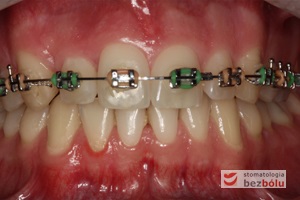

Młody 28-letni, pogodny, stale uśmiechnięty pacjent zgłosił się celem korekcji wad zębowych ograniczających pełną ekspresję uśmiechu. Głównym problemem był dodatkowy siekacz boczny (dwójka) po stronie prawej w łuku górnym. Dodatkowy ząb spowodował stłoczenia pozostałych zębów w łuku górnym oraz przesunięcie linii pośrodkowej. Obliczenia dostępnego miejsca dla siekacza bocznego wpłynęły na wybór zęba przeznaczonego do ekstrakcji. Usunięto dwójkę ustawioną dowargowo, zaś jej „siostrę bliźniaczkę” skierowaną w stronę podniebienia wprowadzono do łuku zębowego w drodze leczenia ortodontycznego. Problemem było szczelne zamknięcie szpary poekstrakcyjnej z powodu nadmiaru miejsca w kości. Wyrównano linię pośrodkową. Leczenie przeprowadzono jednym łukiem ortodontycznym górnym, dolny łuk zębowy nie wymagał założenia aparatu. Po zdjęciu zamków korekcję detali przeprowadzono z użyciem pozycjonera wykonanego w technice termoformingu. Stabilizację efektów leczenia zapewnił stały retainer klejony do powierzchni podniebiennych siekaczy górnych.

Leczenie ortodontyczne: planowanie i aktywna faza leczenia, leczenie retencyjne – lekarz stomatolog Magdalena Żywicka i lekarz stomatolog Marta Pakuła